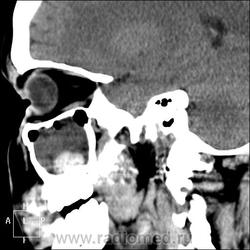

КТ ППН и носоглотки. Девушка 21 года. Полипозный риносинусит.

Госпитализирована для оперативного лечения. Удалены полипы носа. Вторым этапом планируется гайморотомия. Во время операции - подозрение на образование носоглотки. Сохраняется затруднение носового дыхания. Направлена на КТ. Категорически отказалась от контрастировния (лекарственная полиаллергия, боится).

Полип в носоглотке справа. Нарушена пневматизация придаточных пазух носа кроме левой решётчатой. В левой гайморовой на дне неясно что…

На дне гайморовой - полип, в носоглотке немаленький хоанальный полип. Там всё в полипах, а они и фиброзные бывают, и ангиофибромы, и ангиоаденомы... Вот и плотность разная.

Ну, как-то все в одну кучу - и полипы, и ангиофибромы. При ангиофиброме, например, околоносовые пазухи свободны. А гиперденсность более характерна для грибкового поражения (аспергилеза), в том числе и "севшим" на пломбировочный материал.

На операции визуально полипы аденоматозного типа. Какие будут гистологически после гайморотомии - сейчас трудно сказать. Если б гиперденсность была только по нижней стенке верхнечелюстной пазухи, тогда вариант с аспергиллезом на пломбировочном материале, на мой взгляд, был бы более вероятен. У девушки участки гиперденсности по всем стенкам верхнечелюстных пазух, в основной пазухе, совсем чуть - в решетчатом лабиринте слева, без костной деструкции. Без посева и гистологии - только гадать)). В носовой полости признаков грибкового поражения ЛОРы не отмечают. Но Вы правы, может иметь место изолированное поражение синусов.